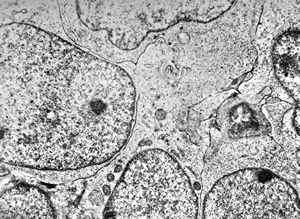

rabbit spinal cord trauma